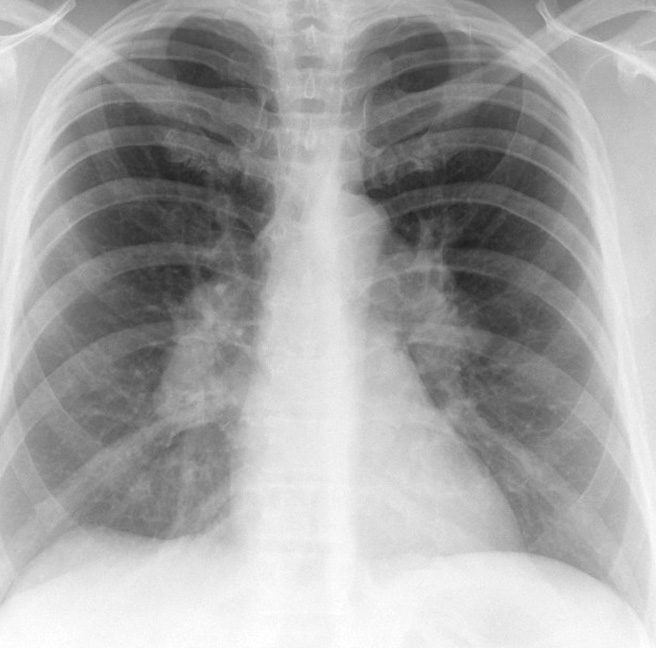

Sarcoid

Cse 1 PA